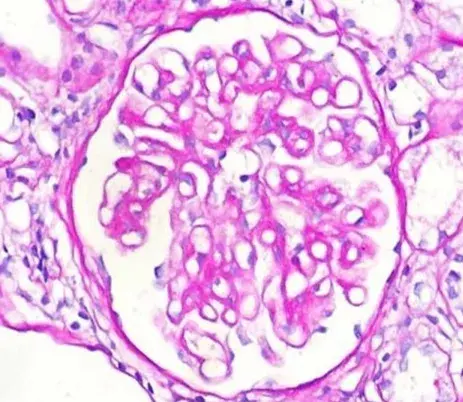

Caso clínico publicado no **[NEJM](https://www.nejm.org/doi/full/10.1056/NEJMicm2213584?query=featured_nephrology)**: Um homem de 35 anos com nefropatia por IgA procurou pronto-socorro com quadro de confusão mental, visão embaçada e convulsão há 01 dia. Duas semanas antes da apresentação ele começou a tomar ciclosporina para tratamento de nefropatia por IgA. Sua PA era de 160/80 mm Hg.

Nefropatia Membranosa: e se o paciente não responder ao tratamento inicial?

Nefropatia Membranosa: e se o paciente não responder ao tratamento inicial?

Como fazer o tratamento da Nefropatia Membranosa de forma prática!

Como fazer o tratamento da Nefropatia Membranosa de forma prática!